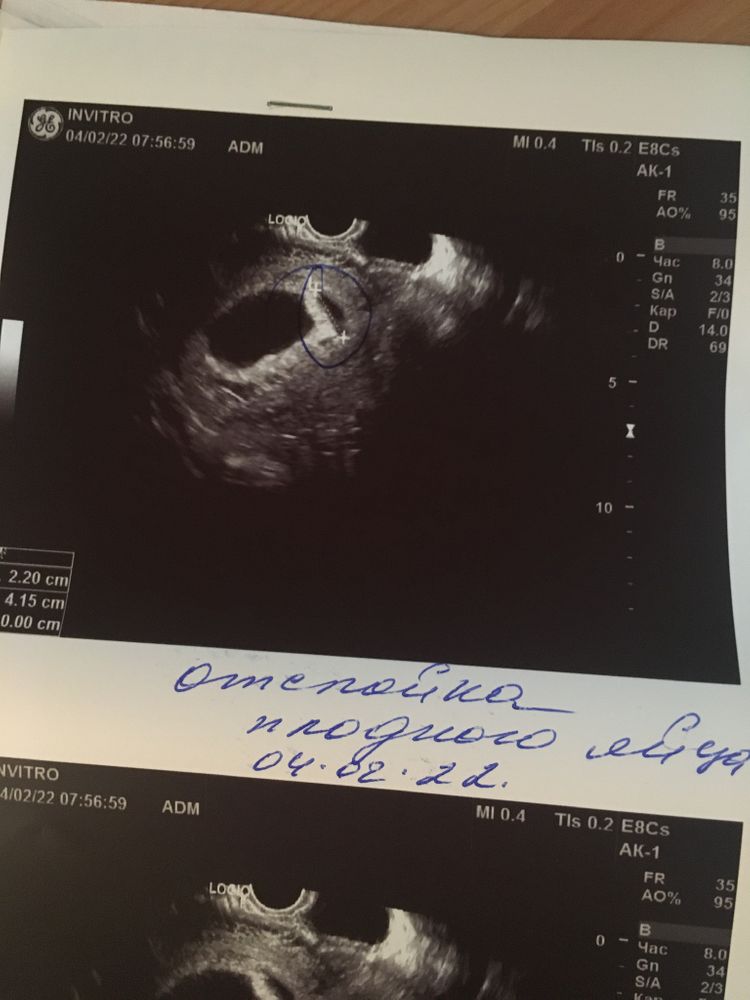

Узи первого триместра форум

Узи первого триместра форум 117 фото